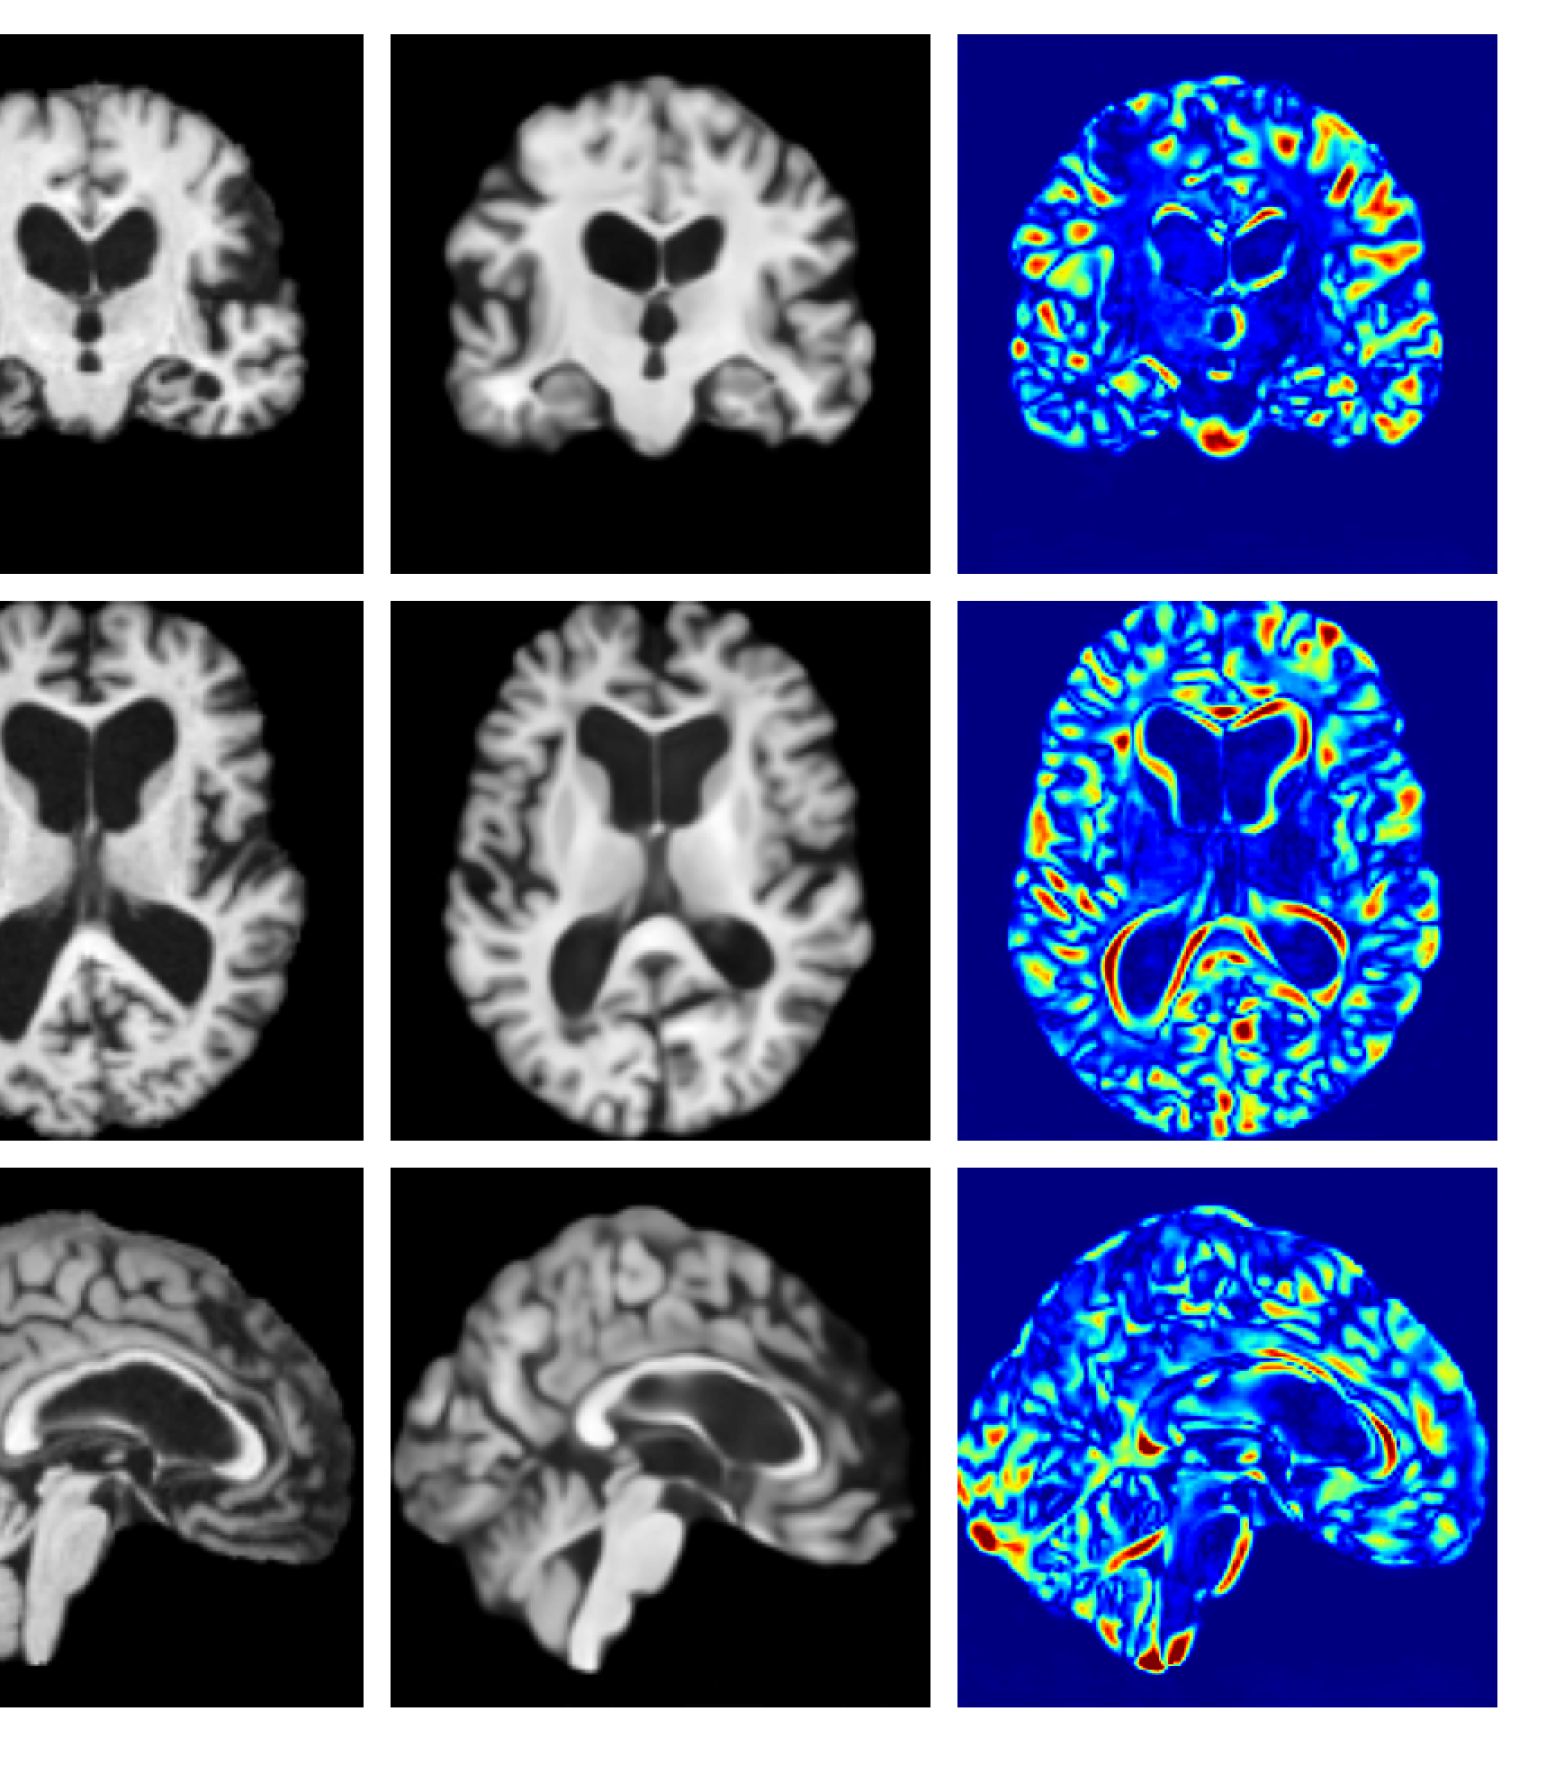

Figure 3: Example reconstructions and anomaly maps for a sample from the disease cohort of the UKBB dataset. Lesion and WMH are indicated in the original image by the red and yellow boxes respectively.

Figures 3 and 4, show example reconstructions and abnormality maps for a sample from the UKBB and UoTH datasets, respectively. Enlarged figures and additional example qualitative results for the ADNI dataset are available in the Supplementary. In Figure 3 we see that whilst all models are able to detect the lesion visible in the sagittal slice, the VAE, cVAE, LDM and LDM (TavgT_{avg}) produce very smooth outputs or lose defining characteristics and thus exhibit more false positives in healthy tissue. THOR and CADD provide the best results, with CADD better detecting white matter hypointensities (WMH). However, neither method fully inpaints all WMH, potentially due to presence of WMH in the healthy training set.

Figure 7 provides example reconstructions and anomaly maps for a healthy subject from the UK Biobank holdout test cohort.

Figure 7: Example healthy reconstructions and anomaly maps for a sample from the UK Biobank healthy test cohort. For a healthy subject, we should observe no regions highlighted in the anomaly map.